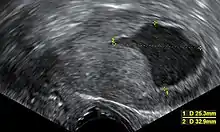

Nos Estados Unidos, tem sido cada vez mais usada a ecografia transvaginal para examinar a espessura do endométrio em mulheres com hemorragias pós-menopausa, de modo a auxiliar o diagnóstico de cancro do endométrio.[38] No Reino Unido, tanto a biópsia endometrial quanto a ecografia transvaginal, usadas em conjunto, são o tratamento padrão para o diagnóstico de cancro do endométrio.[15] A homogeneidade do tecido visível na ecografia transvaginal pode ajudar a indicar se a espessura é cancerosa. As descobertas da ecografia por si só não são conclusivas em casos de cancro do endométrio, pelo que deve ser usada em conjunto com outro método de rastreio (por exemplo, biópsia endometrial). Outros exames imagiológicos são de uso limitado. As TAC são usadas para imagens pré-operatórias de tumores que parecem avançados no exame físico ou têm um subtipo de alto risco (com alto risco de metástase).[39] Eles também podem ser usados para investigar doenças extrapélvicas.[15] Uma ressonância magnética pode ser útil para determinar se o cancro alastrou-se para o colo do útero ou se é um adenocarcinoma endocervical.[39] A ressonância magnética também é útil para examinar os nódulos linfáticos próximos.[15]